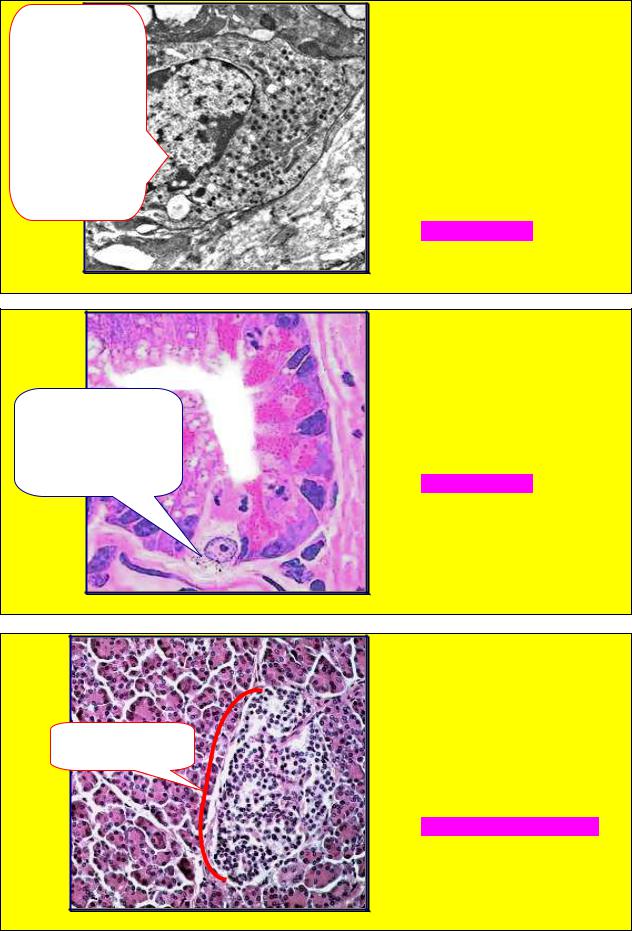

ЗАДАНИЕ 1.104 |

структуру (скобка), в составе |

1.Эндокриноциты. |

2. Эндотелиоциты. |

на рис.1.104 клетки. Назовите |

данную структуру. |

А. Псевдофолликул. |

Б. Трабекула. |

В. Эндокринный островок. |

Г. Фолликул. |

Д. Концевой отдел. |

Рис. 1.104 |